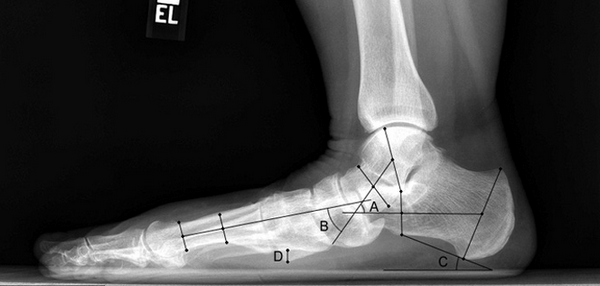

Рентген плоской стопы.

Основными методиками, используемыми для диагностики и определения степени продольного плоскостопия, являются подометрия, плантометрия и рентгенография стоп. Самый простой и доступный способ - вычисление подометрического индекса по методу Фридланда. Для этого производят измерение высоты стопы от вершины свода до пола и длины стопы от края пятки до конца I пальца. Затем высоту стопы умножают на 100 и делят на длину. Полученная цифра - подометрический индекс, который в норме должен составлять 29-31. При уменьшении индекса до 27-29 можно заподозрить начальные степени плоскостопия. Если индекс составляет около 25, речь идет о резко выраженном дефекте.

Для уточнения степени патологических изменений применяют плантографию и рентгенографию. Плантография представляет собой исследование, в ходе которого подошвенную поверхность стоп покрывают красящим веществом, а затем исследуют отпечатки на бумажном листе. Рентгеновские снимки выполняют в боковой проекции, после чего отправляют на описание к рентгенологу, который измеряет расстояние и углы между отдельными костями стопы.